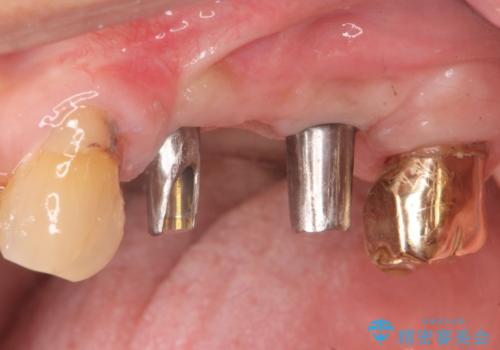

- 奥歯を失い半年間入れ歯を使用してみたが、とにかく咬めない、食事を楽しむことができない!と

咬合機能の回復を求めて来院されました。

しっかりとまた物を噛めるようになるために、インプラントを用いて咬合機能を回復していきます。

- 106.7万円(インプラント×2・チタンカスタムアバットメント×2・ジルコニアクラウン×3・仮歯×3)費用は治療当時の料金となります